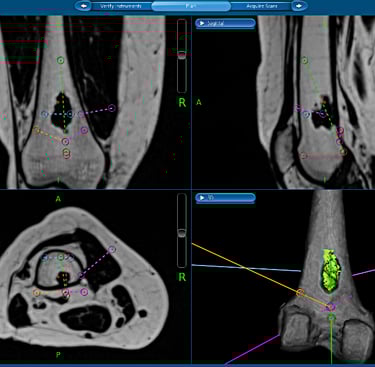

Management of these tumours can be very complex and Mr Pang is one of a few surgeons in Melbourne who has extensive experience in the surgical management of bone and soft tissue tumours / sarcomas. Management often include collaboration with other specialists of with similar interests (plastics, spinal and thoracic surgeons), complex resections such as the pelvis, utilisation of tumour / megaprosthesis and employing advanced computer navigation techniques to achieve precision tumour surgery.